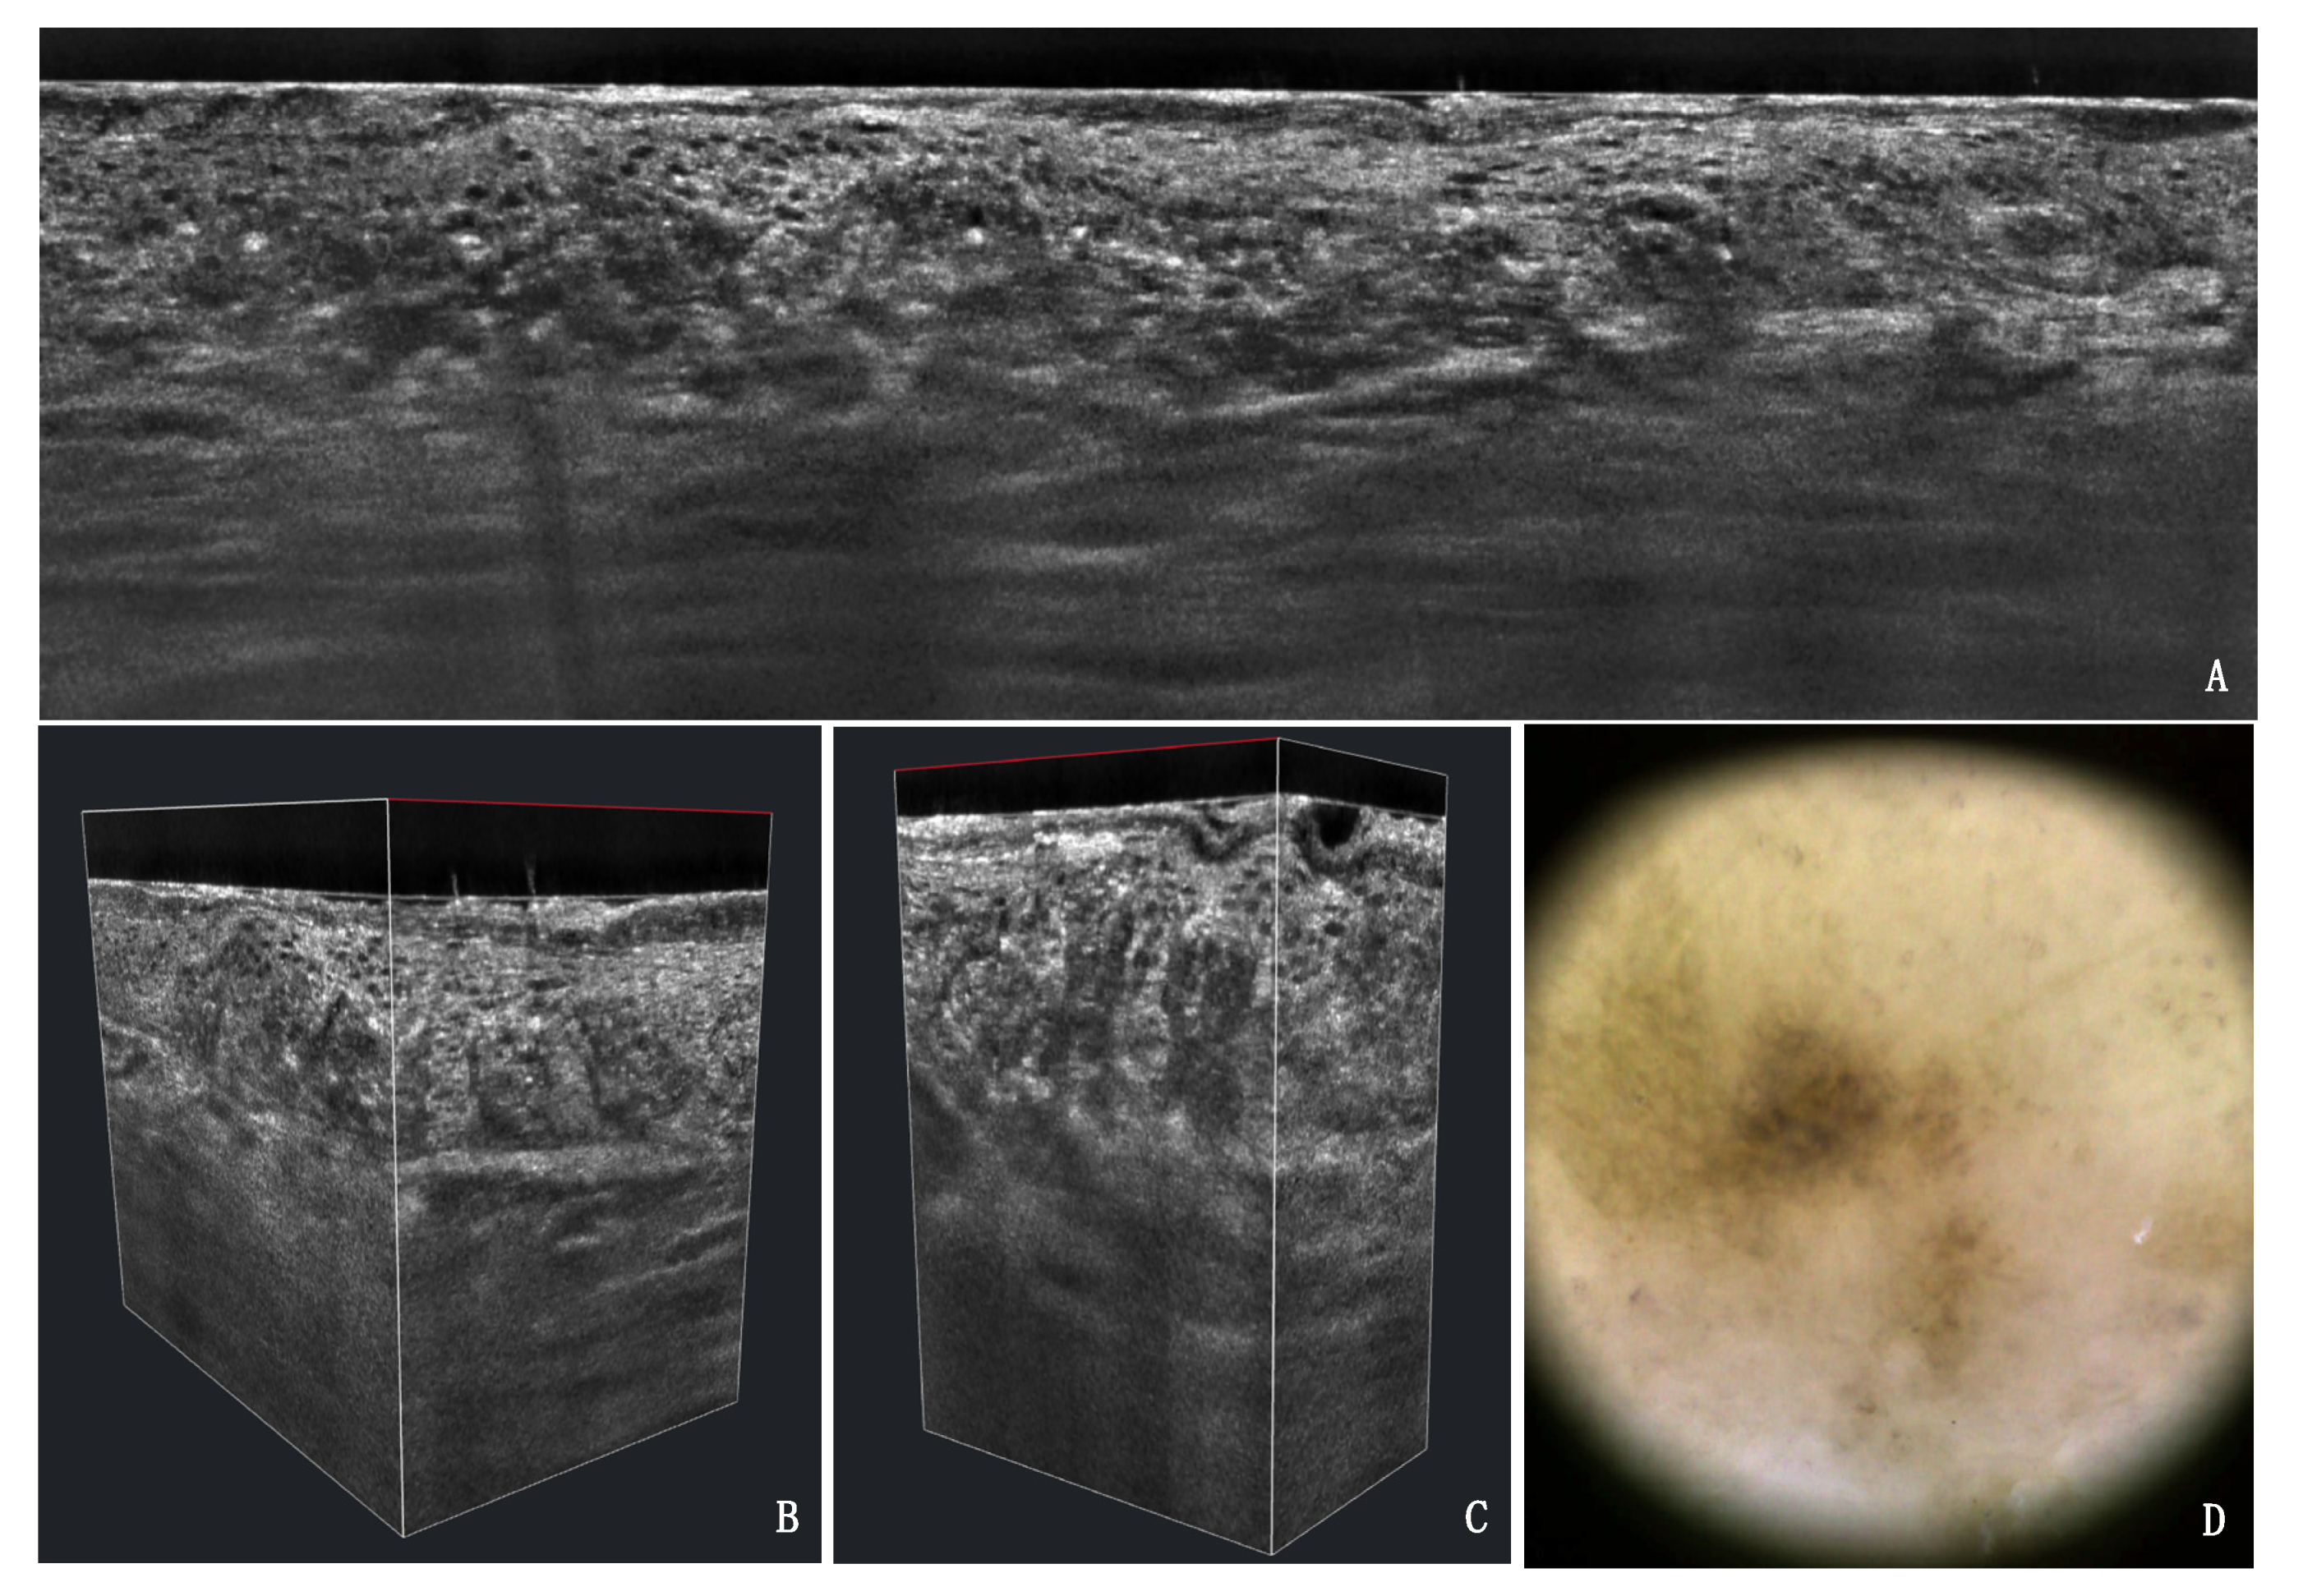

In-Vivo LC-OCT Evaluation of the Downward Proliferation Pattern of Keratinocytes in Actinic Keratosis in Comparison with Histology: First Impressions from a Pilot Study

3. Results

3.1. PRO Grading

3.2. Agreement